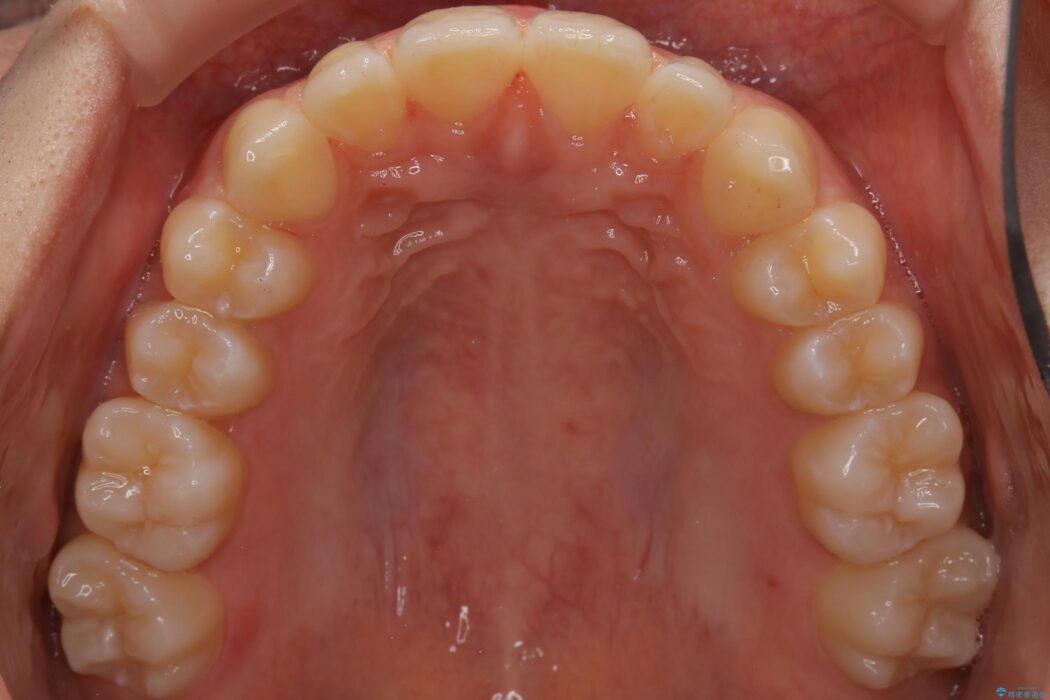

すきっ歯を改善したいとご来院された患者様です。

インビザライン・クリンチェック(シミュレーション)を行い、インビザラインライトで治せる範囲であると診断し、矯正治療を行いました。

マウスピース14枚・期間4ヶ月で主訴であるすきっ歯を改善し、治療を終えることが出来ました。